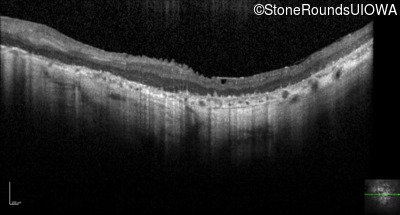

Optical Coherence Tomography - Right - Hand Motion sc

Exemplar / OCT Stack

OCT Stack